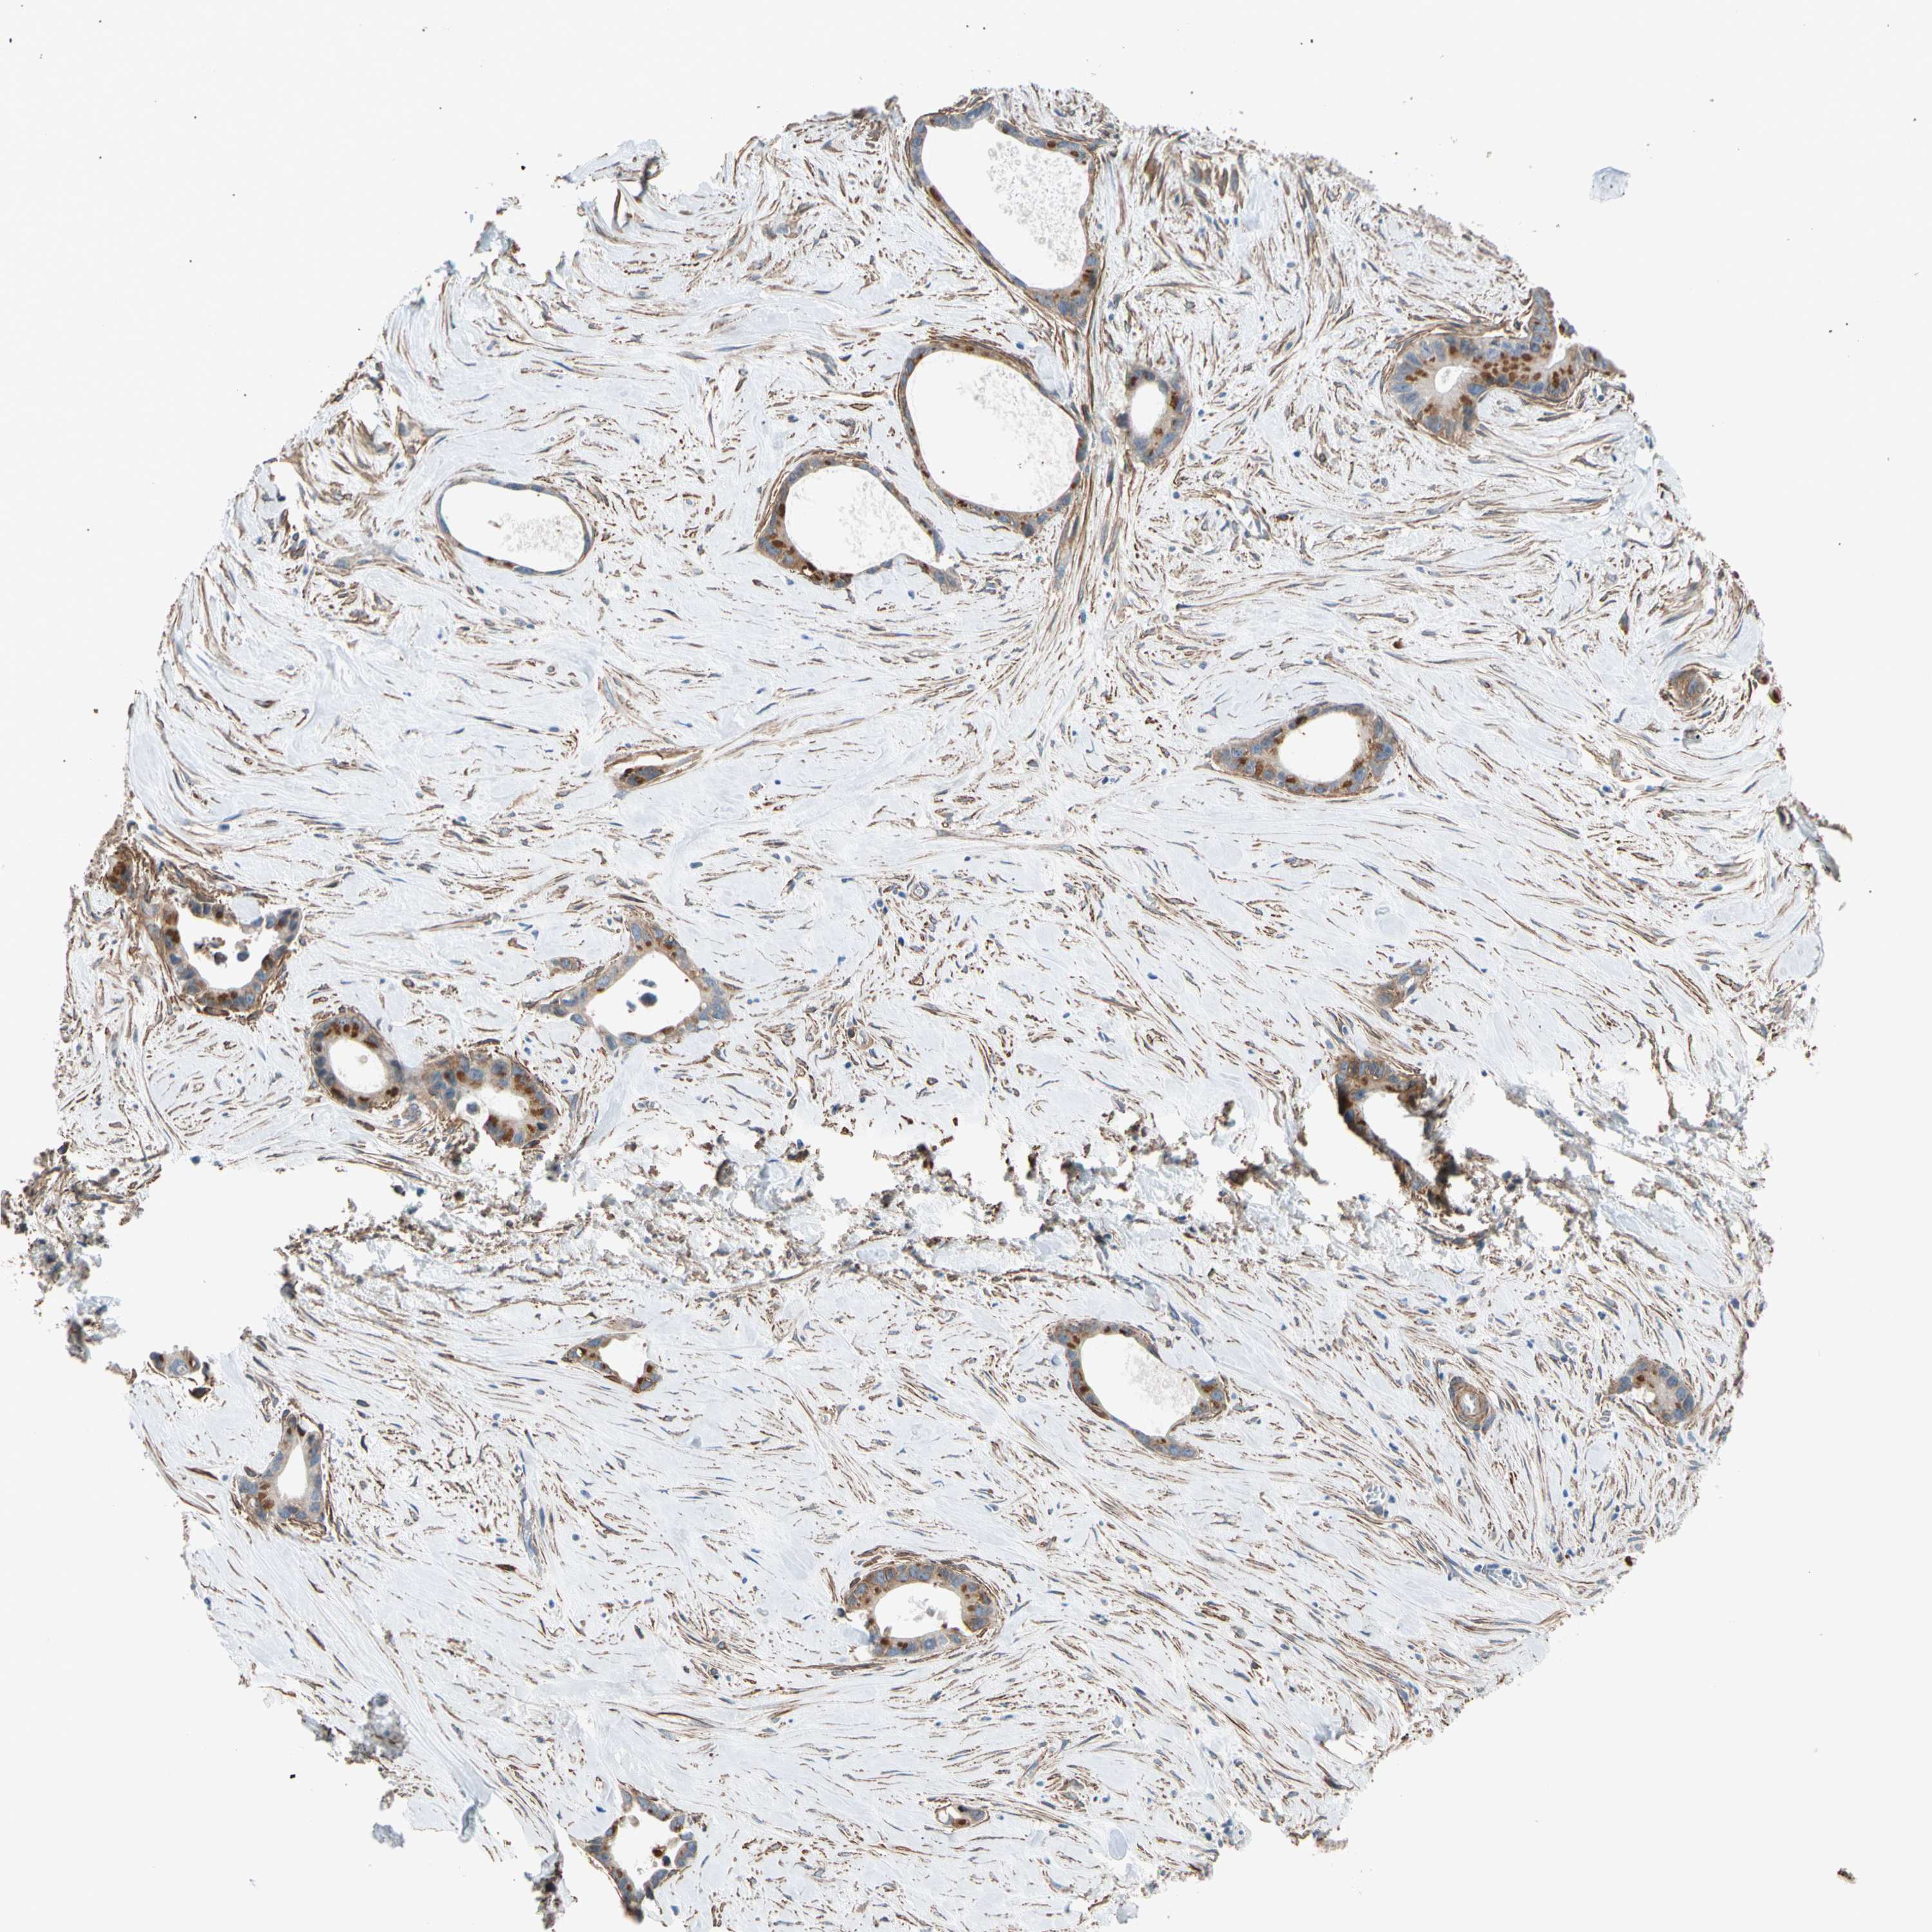

LIVER CANCER - Protein expressioni

A mouse-over function shows sample information and annotation data. Click on an image to view it in a full screen mode. Samples can be filtered based on level of antibody staining by selecting one or several of the following categories: high, medium, low and not detected. The assay and annotation is described here.

Note that samples used for immunohistochemistry by the Human Protein Atlas do not correspond to samples in the TCGA dataset.

Antibody stainingi

Antibody staining in the annotated cell types in the current human tissue is reported as not detected, low, medium, or high, based on conventional immunohistochemistry profiling in selected tissues. This score is based on the combination of the staining intensity and fraction of stained cells.

Each image is clickable and will lead to virtual microscopy that enables deeper exploration of all samples and also displays staining intensity scores, fraction scores and subcellular localization as well as patient and tissue information for each sample.

Antibody HPA008183

Antibody HPA053882

Antibody CAB019313

Staining

High

Medium

Low

Not detected

Intensity

Strong

Moderate

Weak

Negative

Quantity

>75%

75%-25%

<25%

None

Location

Nuclear

Cytoplasmic/membranous

Cytoplasmic/membranous,nuclear

Cholangiocarcinoma

Carcinoma, Hepatocellular, NOS